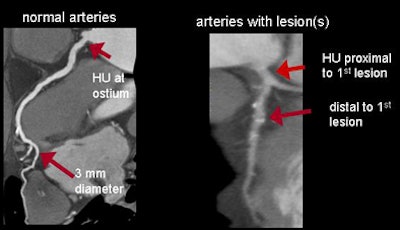

For normal vessels, the team first assessed whether contrast opacification gradients might carry information related to the level of stenosis. To do this, they approximated the continuous change of HU along the vessel by using only two points: in normal arteries, the HU measured at the ostium and where each artery tapered to 2.5 mm in diameter. For diseased vessels, the gradient was similarly approximated by the difference in HU measured immediately proximal and distal to the most proximal lesion.

| The gradient or change in HU along the course of the vessel was defined as the difference in HU at the ostium and the point where each artery tapered to 2.5 mm in diameter. For diseased vessels, the gradient was obtained immediately proximal and distal to the most proximal lesion (above). Measurements were obtained every 1 mm and analyzed to determine the distance from ostium, mean HU, lumen area, and short-axis diameter (below). All images courtesy of Dimitris Mitsouras, Ph.D., and Dr. Frank Rybicki, Ph.D. |